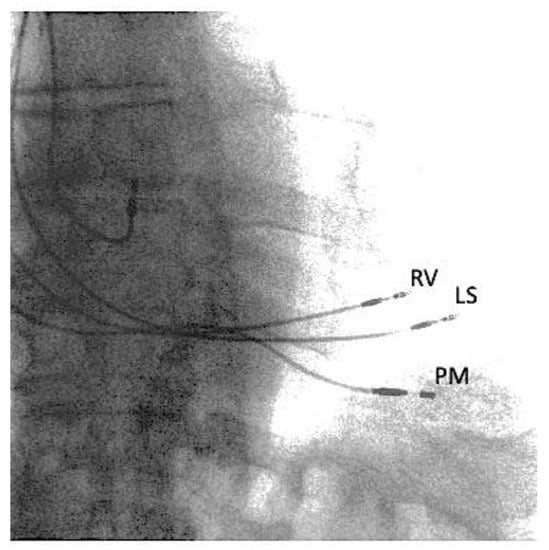

2. Case Report